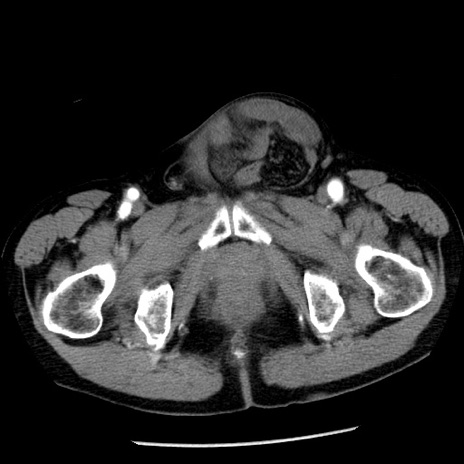

症例26(横断像)

【症例】80歳代男性

【主訴】嘔吐

【現病歴】昨晩2回嘔吐あり、今朝になっても嘔吐あり。来院。

【既往歴】胃潰瘍

【身体所見】意識清明、BT 37.6℃、BP 166/95mmHg、HR 100bpm、SpO2 97%、腹部:平坦・軟、腸蠕動音聴取良好、圧痛なし。

【データ】WBC 21900、CRP 1.46